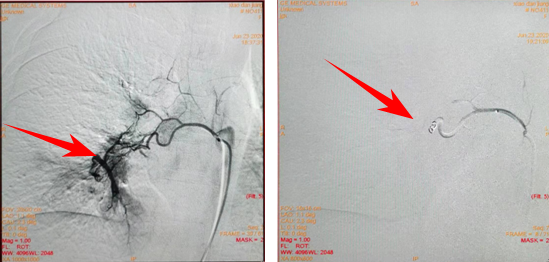

6月19日,在中心醫(yī)院介入科全凌峰主任指導(dǎo)下,兒童心胸血管中心副主任醫(yī)師劉敬,主治醫(yī)師李思和主治醫(yī)師許輝共同協(xié)作完成了支氣管肺動(dòng)脈造影;造影結(jié)果顯示:右支氣管動(dòng)脈-肺動(dòng)脈瘺。明確了診斷,下一步就是治療,為此,科室再次組織討論,制定下一步手術(shù)計(jì)劃,并邀請(qǐng)廣州市婦女兒童醫(yī)療中心李海波教授現(xiàn)場(chǎng)指導(dǎo)。6月23日,一切準(zhǔn)備就緒,小單再次進(jìn)入手術(shù)室,這一次兒童心胸血管中心的手術(shù)團(tuán)隊(duì)?wèi)?yīng)用介入技術(shù),順利的將異常血管栓塞成功。整個(gè)過(guò)程歷時(shí)1個(gè)小時(shí),由于介入手術(shù)屬于微創(chuàng)手術(shù),小單在整個(gè)過(guò)程中都是保持清醒狀態(tài),當(dāng)李思主治醫(yī)師最后告訴小單手術(shù)非常成功,以后不會(huì)再咳血了,小單臉上展現(xiàn)了久違的笑

負(fù)責(zé)兒童外周血管介入方向的李思主治醫(yī)師介紹,支氣管動(dòng)脈-肺動(dòng)脈瘺是先天性支氣管動(dòng)脈-肺動(dòng)脈畸形的一種,是體循環(huán)動(dòng)脈-肺動(dòng)脈畸形其中的一種類型,表現(xiàn)為支氣管動(dòng)脈與肺動(dòng)脈間的異常溝通,屬于罕見(jiàn)的肺部血管畸形。另外,體動(dòng)脈也可來(lái)源,多見(jiàn)于內(nèi)側(cè)乳房動(dòng)脈,肋間動(dòng)脈,主動(dòng)脈異常分支,心外膜動(dòng)脈,心包動(dòng)脈,食管動(dòng)脈和胸壁動(dòng)脈。本病常于成年后發(fā)病,兒童患者少見(jiàn)。部分患者終身可無(wú)任何臨床表現(xiàn),而大多數(shù)以大咯血為首發(fā)癥狀,嚴(yán)重者可出現(xiàn)休克甚至死亡,或由于不能及時(shí)將血凝塊咯出,而導(dǎo)致阻塞性肺不張或呼吸道梗阻等,屬于內(nèi)科急癥,需要緊急救治。而數(shù)字減影血管(dsa)造影技術(shù)對(duì)支氣管動(dòng)脈-肺動(dòng)脈畸形有確診意義,可以觀察支氣管動(dòng)脈及其分支走行、形態(tài)、側(cè)支供血、病變區(qū)血管形態(tài)、畸形口的數(shù)目和位置,是診斷的金標(biāo)準(zhǔn)。造影后可進(jìn)一步在dsa引導(dǎo)下介入行異常動(dòng)脈栓塞術(shù),由于創(chuàng)傷小、安全性高、療效確切、術(shù)后恢復(fù)快,目前成為臨床治療的首選方式。